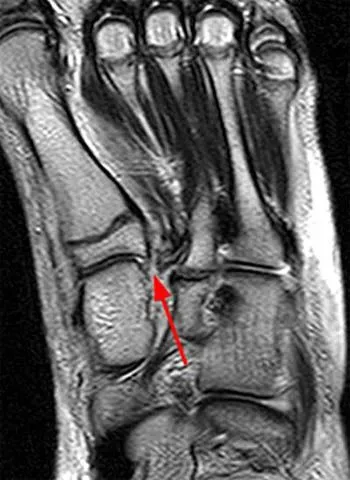

Below is an MRI image demonstrating the location of the Lis Franc's ligament with the ligament ruptured (red arrow).